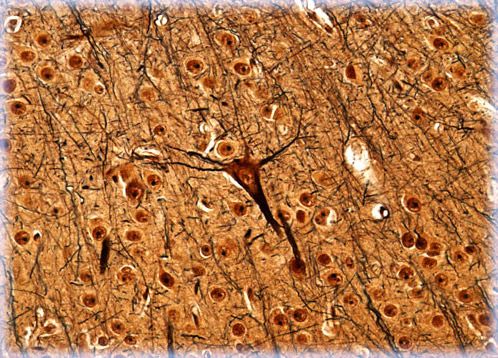

Humans have been intrigued by the origin of intelligence for thousands of years, although some early philosophers believed that the acumen was located in the heart, not the brain. Significant insight into the true function of the brain was not gained until the eighteenth century when Italian physiologist Luigi Galvani demonstrated that electricity existed inside brain cells.